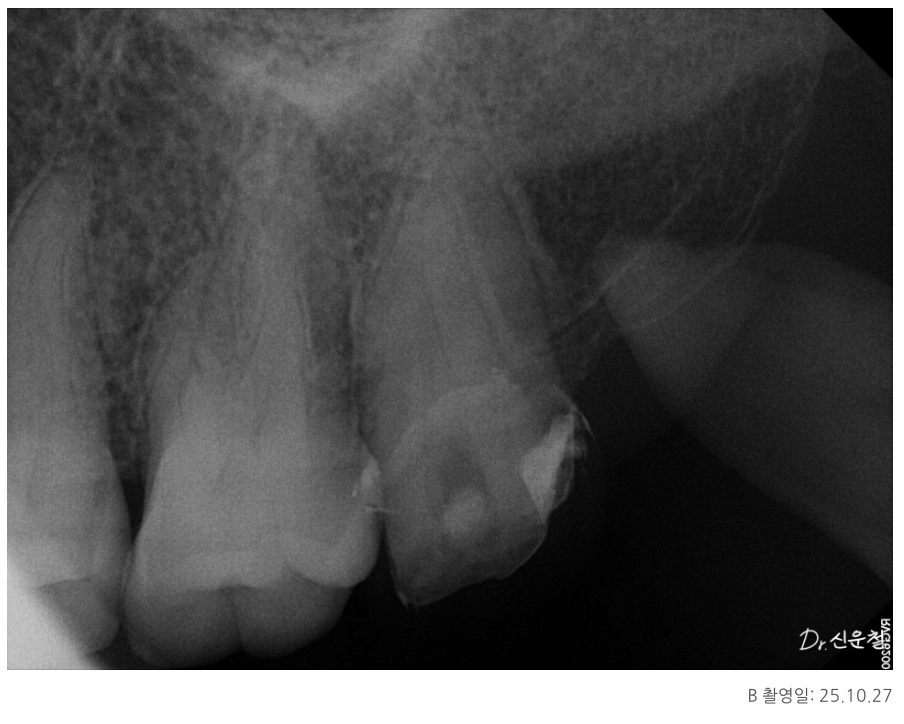

실제 내원 사례 중에는

이미 신경치료를 받은 어금니에서

잇몸이 다시 붓고 고름이 차

발치 진단을 받고 오신 분도 계셨습니다.

또 다른 분은

“신경치료가 어렵다”는 설명을 듣고

의뢰로 내원하신 경우였습니다.

방사선 사진에서 신경관이 잘 보이지 않거나

CT에서 신경이 있어야 할 자리가

빈 공간이 아닌 뼈처럼 보이는 경우가 이에 해당합니다.